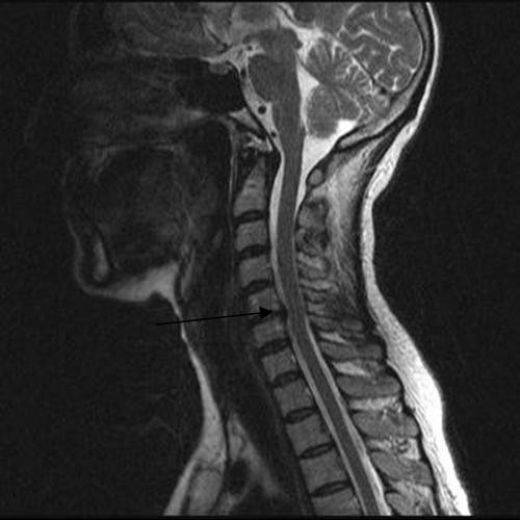

Boyun Fıtığı Ameliyatı: Riskleri ve Sonrası Boyun fıtığı, tıbbi olarak servikal disk hernisi olarak adlandırılan bir durumdur ve omurganın boyun bölgesinde yer alan disklerin kayması veya yırtılması sonucu ortaya çıkar. Bu durum, sinir köklerine veya omuriliğe baskı yaparak çeşitli semptomlara yol açabilir. Boyun fıtığı ameliyatı, konservatif tedavi yöntemlerinin başarısız olduğu durumlarda önerilen cerrahi bir müdahaledir. Ancak, bu tür bir ameliyatın riskleri ve sonrası hakkında bilgi sahibi olmak önemlidir. Ameliyatın Riskleri Boyun fıtığı ameliyatının bazı potansiyel riskleri bulunmaktadır. Bu riskler, her cerrahi işlemde olduğu gibi değişkenlik gösterebilir. Aşağıda bu riskler detaylandırılmıştır: